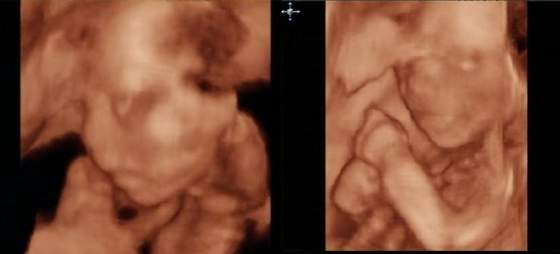

Jaki wstydniś na fotce. Tak się zasłaniał

a wiesz że Ignaś ma takie samo zdjęcie? Identycznie się zasłaniał:-). Czasem się naprawdę zastanawiam czy dzidziuś czuje że się go podgląda;-)

wszyscy znajomi jak jeden mąż wróżyli mi chłopca, a ja wiedziałam, że dziewczynka:-) i nie pomyliłam się:-) Dziołcha na 120%:-) Wsio jest w jak najlepszym porządku